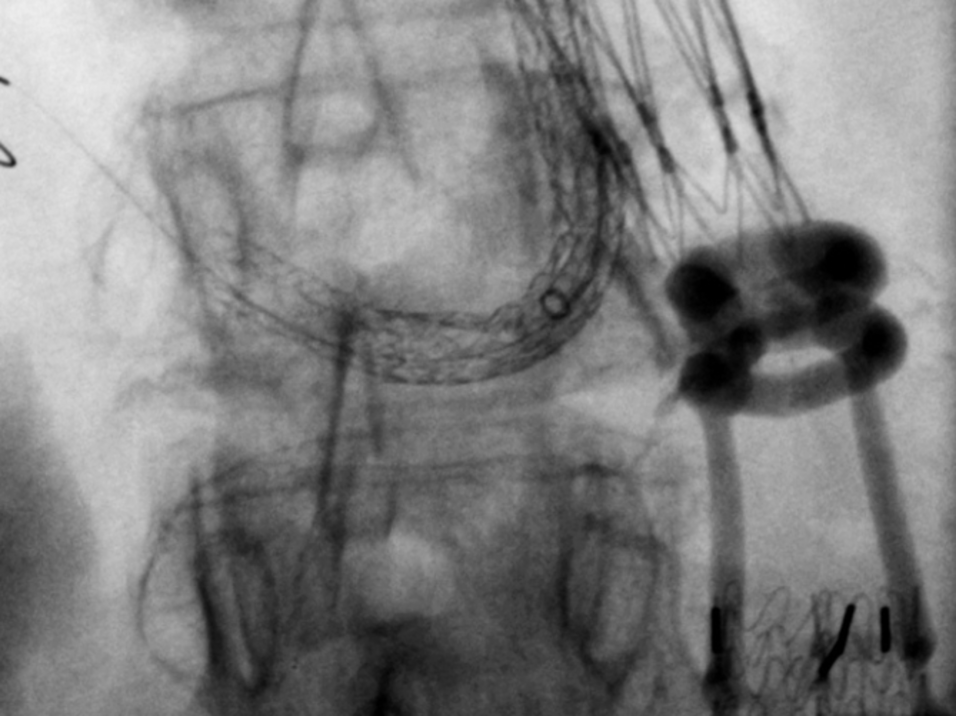

Abhängig von Ausdehnung und Lokalisation des Aneurysmas ist die endovaskuläre Therapie eine minimalinvasive, für die Patient:innen sehr schonende Behandlungsoption. Nach örtlicher Betäubung und gegebenenfalls leichten angstlösenden bzw. beruhigenden Medikamenten führen die Expert:innen der Abteilung für Radiologie und Nuklearmedizin durch die Haut eine übliche Punktion der Leistenarterie als Zugang zum Gefäßsystem durch. Anschließend wird mit Hilfe bildgebender Verfahren über ein Kathetersystem eine ummantelte Gefäßstütze (Aorten-Stentgraft) präzise innerhalb des erkrankten Gefäßabschnittes eingesetzt, um die Gefäßaussackung von innen abzudichten.

Bei einem nicht unerheblichen Anteil der Betroffenen sind keine Standard-Stentgraft-Materialien verwendbar, um eine sichere Abdichtung zu gewährleisten. In diesen Fällen kommen maßgefertigte Stentgraft-Prothesen zum Einsatz. Diese haben abhängig von der Lokalisation Verbindungen zu den übrigen wichtigen Baucharterien wie Nieren und Darm.

Ist die Gefahr eines Aortenrisses sehr hoch, beispielsweise aufgrund eines sehr großen Aneurysmas oder Schmerzsymptomatik durch das Aneurysma, kann die Fertigungszeit der individuell produzierten Aortenstentgrafts von mehreren Wochen nicht abgewartet werden. Alternativ kommen hybride endovaskuläre Techniken zu Einsatz, die Standardmaterialien miteinander kombinieren, um eine umgehende zeitnahe Versorgung durchführen zu können.

Auch eine atypische Versorgung zum Erhalt beispielsweise wichtiger zusätzlicher Nierenarterien zur Förderung der Nierenfunktion sind mit diesen Techniken umsetzbar.